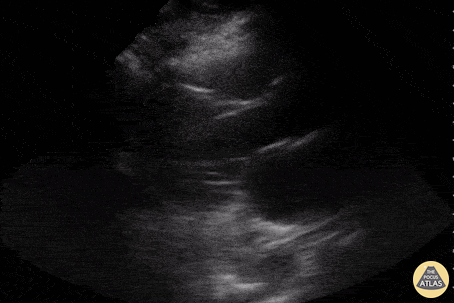

Parasternal long axis view of a 47yo with PMH non-obstructive CAD incidentally found to have mildly reduced LV systolic function and an echogenic mass in LV extending to outflow tract. Determined to be a large LV thrombus of unknown etiology. Andrew Balstera, MD Paul Musgrave, MD (OHSU IM POCUS Fellow) @POCUSaurusDx